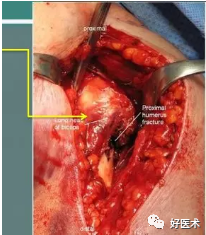

2.肩关节前方入路

优点:

-

切口长,但从三角肌、胸大肌间隙进入,损伤小

适用于肱骨近端各部分骨折及稍远端的肱骨骨折

可向远方延长切口可显露肱骨

部分松解三角肌、胸大肌止点,影响小

从三角肌胸大肌间隙进入,看似切口大,实则损伤小,三角肌易于拉开。

识别肱二头肌长头腱

识别分离的骨块和附着肌腱